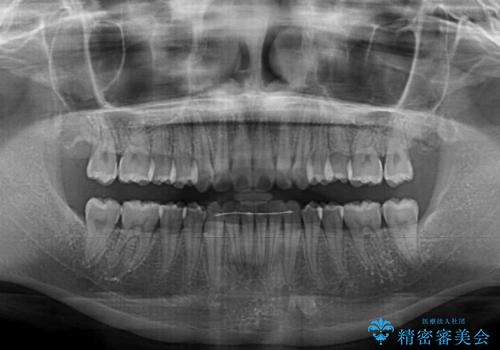

- 前歯のデコボコを気にして来院された患者様です。

前歯が重なっていることで口元が閉じにくくなっていたため、歯列全体の側方への拡大と、歯と歯の間を少し削ってスペースを獲得することとしました。

下顎前歯は後戻りを起こしやすいため、舌側を細いワイヤーで固定し、マウスピース型リテーナーで保定を行うこととしました。